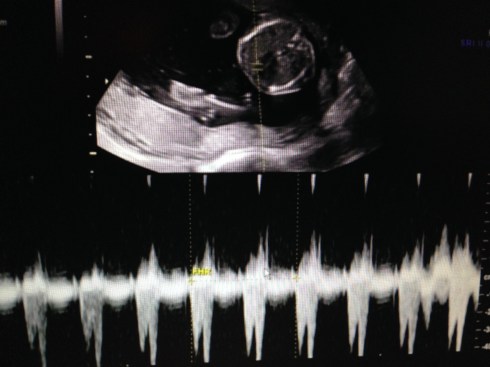

The ultrasound was performed on Friday, March 21, 2014 (at 19 weeks + 4 days). Our boy appeared healthy in all ways and weighed about 10 oz. His growth measurements were between 43% and 62% for his gestational age, and the heart rate was 147 bpm. The placenta is posterior and without previa. My cervix is long. Excellent!

We received a DVD of the scan. I took this short video clip with my phone, that shows baby’s face: moving his jaw, yawning, moving his tongue, and even smiling. You can also see his forearm in front of his face. Watch it again and look for the heart beating. Precious!!

I took these images by pausing the DVD and taking screen shots: